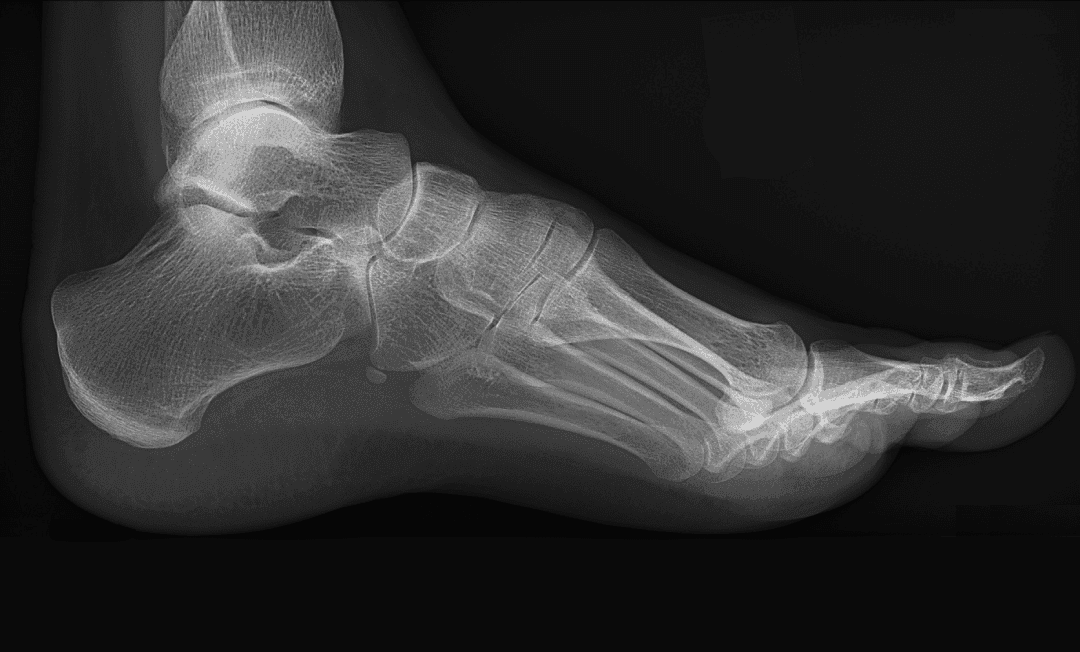

Pes Cavus (Yüksek kavis) Nedir?

Pes cavus, ayak iç kavisinin normalden yüksek olduğu bir durumdur ve halk arasında çukur ayak olarak bilinir. Bu yüksek kavis, ayağın yaylanma kabiliyetini azaltarak işlevselliğini olumsuz yönde etkiler ve yürüme bozukluklarına neden olabilir, bu da diz ve kalça problemlerine yol açabilir. Ağırlık genellikle topuk ve ayak parmaklarının kökünde taşınır, bu da aşırı baskı, ağrı ve instabiliteye yol açar. Ayak şoku iyi absorbe edilemez ve dışa yuvarlanma eğilimi artar, bu da burkulma riskini artırabilir.